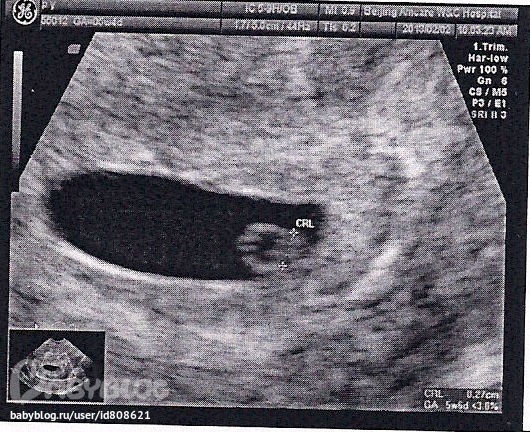

Во-вторых, он отправил меня на трансвагинальное УЗИ на супер пупер чувствительном аппарате, но и пришлось только за УЗИ отдать больше чем 100$, но зато мы с мужем такие счасливые. Мы на мониторе увидели нашу бусинку, ей поставили срок 5 недель и 6 дней, то есть на 2 дня больше чем по реальному акушерскому сроку. А еще показывали как у бусинки пульсирует сердечко и даже включили звук и дали послушать.

Господи, это так мило, у такой крошки и уже бьется сердечко. Сказали что оно только-только начало пульсировать, так как всего 98 ударов минуту. В общем я не ожидала что на 5 неделе там что-то можно разглядеть, видимо не зря так дорого, и правда чувствительный аппатат.

А вот и наше первое фото:

Имплантация по передней стенке матки, как и прошлый раз (может потому что я сплю на животе?))))

Плодное яйцо 2.1х2.2х0.8 см, и моя бусинка 0.3 см.